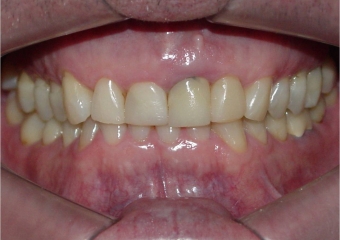

Sorriso final